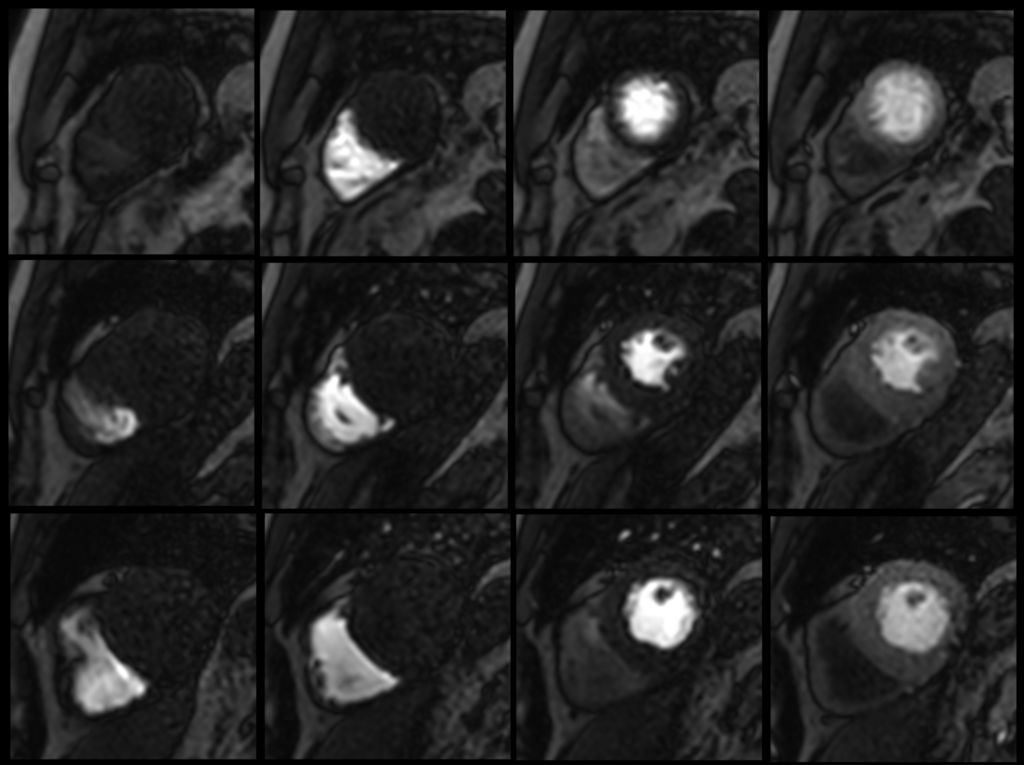

Cardiac Expert supports the acquisition of multi-slice, dynamic tissue studies with T1 weighting and uniform tissue suppression¹ by including Look Locker methods for determining an optimal inversion delay time. Cardiac Expert also provides myocardial tagging² to allow assessment of regional wall motion and allows for real-time interactive planning of challenging cardiac views.

• Multi-slice dynamic study

Multi-slice dynamic study